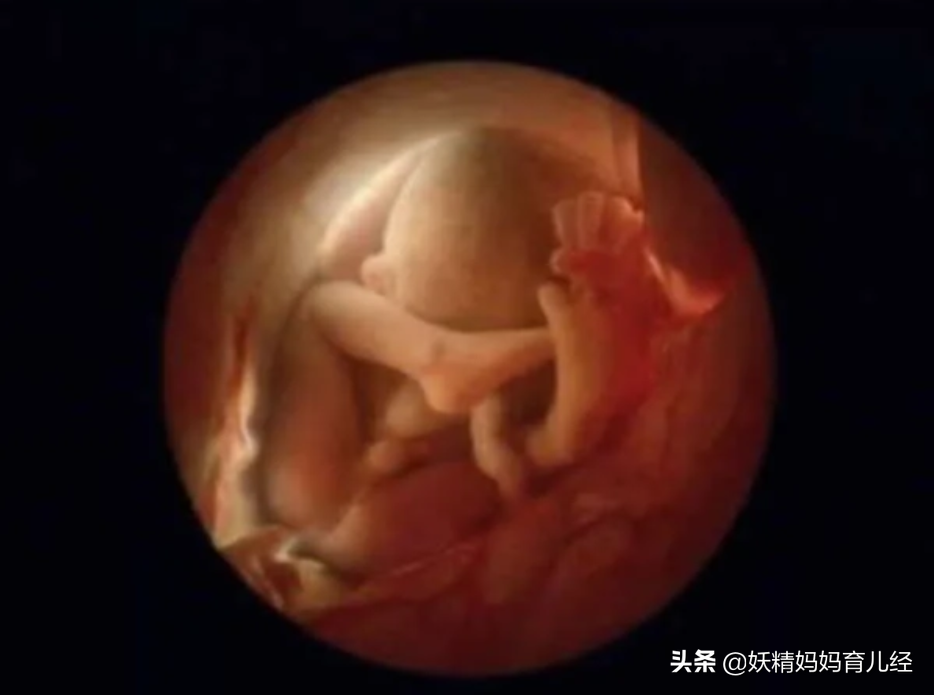

12、怀孕后的16周,胎儿四肢开始活动,探索周边的世界了。这时候,很多孕妇开始感觉到胎动了。但是,宝宝的皮肤还是透明的,可以清晰看到内部的血管。